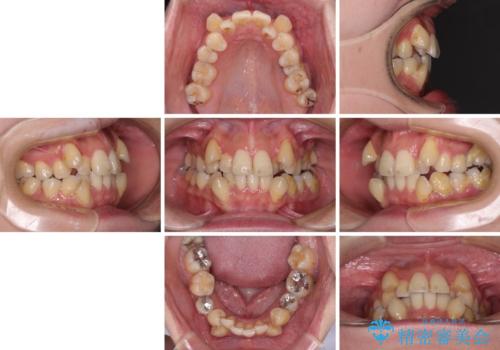

- 上下前歯のデコボコを気にして来院された患者様です。

デコボコが強いため、非抜歯で矯正をすると出っ歯仕上がりとなるため、上下左右の第一小臼歯4本を抜歯することとしました。